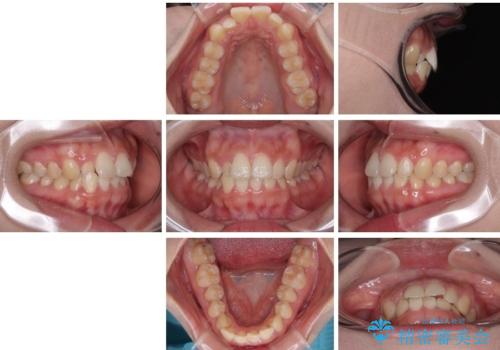

目立ちにくい表側装置で1年完了!狭いアーチを側方拡大し前歯のデコボコを整えた症例

- 前歯のデコボコが気になるでのことで来院された患者様です。

歯列アーチが狭くスペース不足により前歯がデコボコしている状態でした。見た目を改善しつつ、前歯を前方に突出させず、自然な笑顔を目指したいというご希望でした。

治療終了時

前歯が自然なアーチにきれいに並び、正中(上下の中心線)も整い、咬み合わせも良好です。

側方拡大することで、非抜歯であるにも関わらず前歯が前方に出ることなく、バランスの良い仕上がりとなりました。

「矯正装置が目立たず、思ったより短期間で仕上がりに満足しています。鏡を見るのが毎日楽しみになりました!」とうれしいお言葉をいただきました。